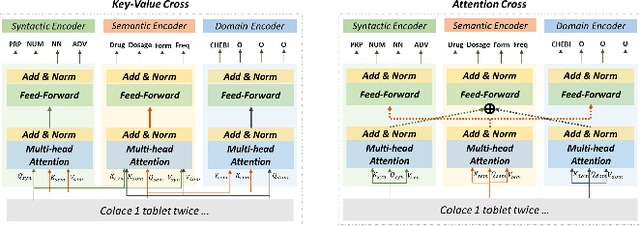

Extracting meaningful drug-related information chunks, such as adverse drug events (ADE), is crucial for preventing morbidity and saving many lives. Most ADEs are reported via an unstructured conversation with the medical context, so applying a general entity recognition approach is not sufficient enough. In this paper, we propose a new multi-aspect cross-integration framework for drug entity/event detection by capturing and aligning different context/language/knowledge properties from drug-related documents. We first construct multi-aspect encoders to describe semantic, syntactic, and medical document contextual information by conducting those slot tagging tasks, main drug entity/event detection, part-of-speech tagging, and general medical named entity recognition. Then, each encoder conducts cross-integration with other contextual information in three ways: the key-value cross, attention cross, and feedforward cross, so the multi-encoders are integrated in depth. Our model outperforms all SOTA on two widely used tasks, flat entity detection and discontinuous event extraction.